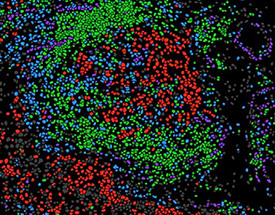

Images

The RI-MUHC respects public health guidelines to reduce transmission of COVID-19. Some images in this report were taken prior to the pandemic.